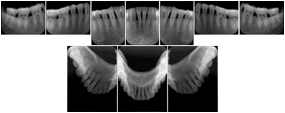

2. A patient requests cosmetic surgery to enhance their facial appearance. The case requires consultation between an orthodontist in New York and an oral surgeon in California. The cephalometric series of 2D projections constructed from a volumetric CT data set that is used for the discussion is arranged by a Structured Display for transfer between the two practitioners.

Cephalometric Series Structured Display

Figure OO-2. Cephalometric Series Structured Display